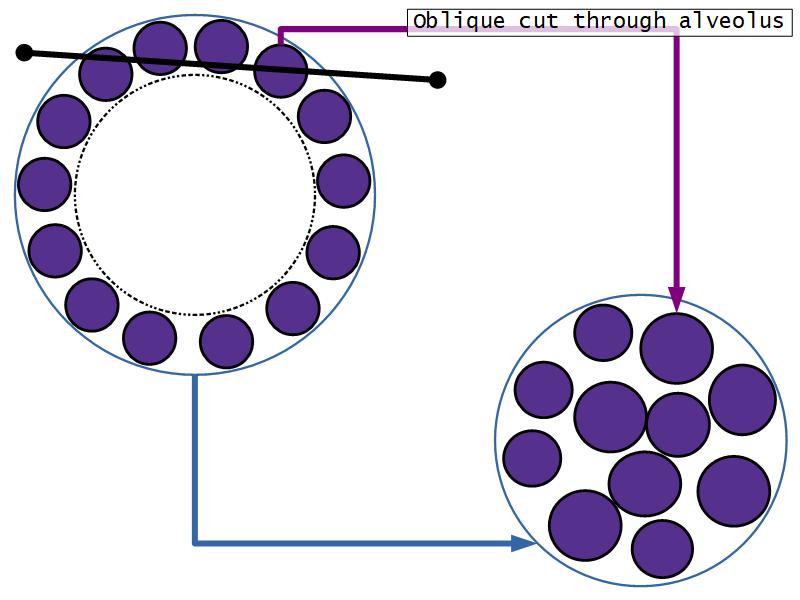

Resting and active

Describe the resting mammary gland and compare with the active gland.

(8)

Resting gland

- Connective tissue dominate

- More adipose tissue

- Glandular tissue reduced

Active gland

- Terminal ducts expand

- Forms alveoli

- Connective tissue reduced

- Adipose tissue reduced

- Glandular tissue dominate